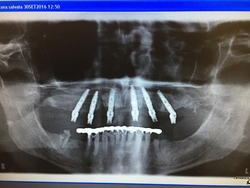

Il venerdì 30 mattina in seduta congiunta (odontotecnici e Clinici ) presenti, hanno assistito all’analisi alla programmazione e all’esecuzione di un’intervento chirurgico complesso in Live Surgery con l’ausilio di guide chirurgiche secondo la tecnica SpeedyGuide.

L’utilizzo del nuovo kit chirurgico per Guidata Isomed e gli impianti Progressive hanno messo in evidenza come sia necessaria ergonomia e precisione nelle componenti meccaniche al fine di ottenere il superamento dei vari ostacoli che spesso questa tipologia d’intervento ci presenta.

L’intervento si è concluso con successo con la messa in opera di una protesi a carico immediato Precostituita tipo all-on-six, impiegando una componentistica protesica progettata appositamente per facilitare l’istallazione di questi manufatti anche nelle situazioni più difficili.

Le conclusioni finali e le verifiche radiologiche hanno confermato l’efficenza del metodo dei materiali impiegati oltre che la grande esperienza del Clinico relatore, con grande apprezzamento dei partecipanti e degli organizzatori del corso.